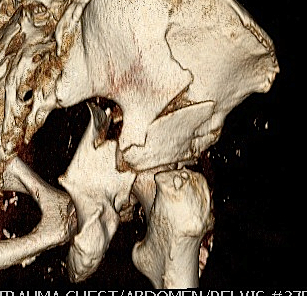

CT reconstruction

- remove head to view acetabulum

- beware volume averaging

- used to guide surgery

Complex / More than one primary fracture line

1. Posterior column & posterior wall

2. Transverse & posterior wall

3. T-shaped

- transverse through acetabulum

- inferior fracture line to obturator foramen

4. Anterior & posterior hemi-transverse

5. Both column

- Y Shaped transverse above acetabulum